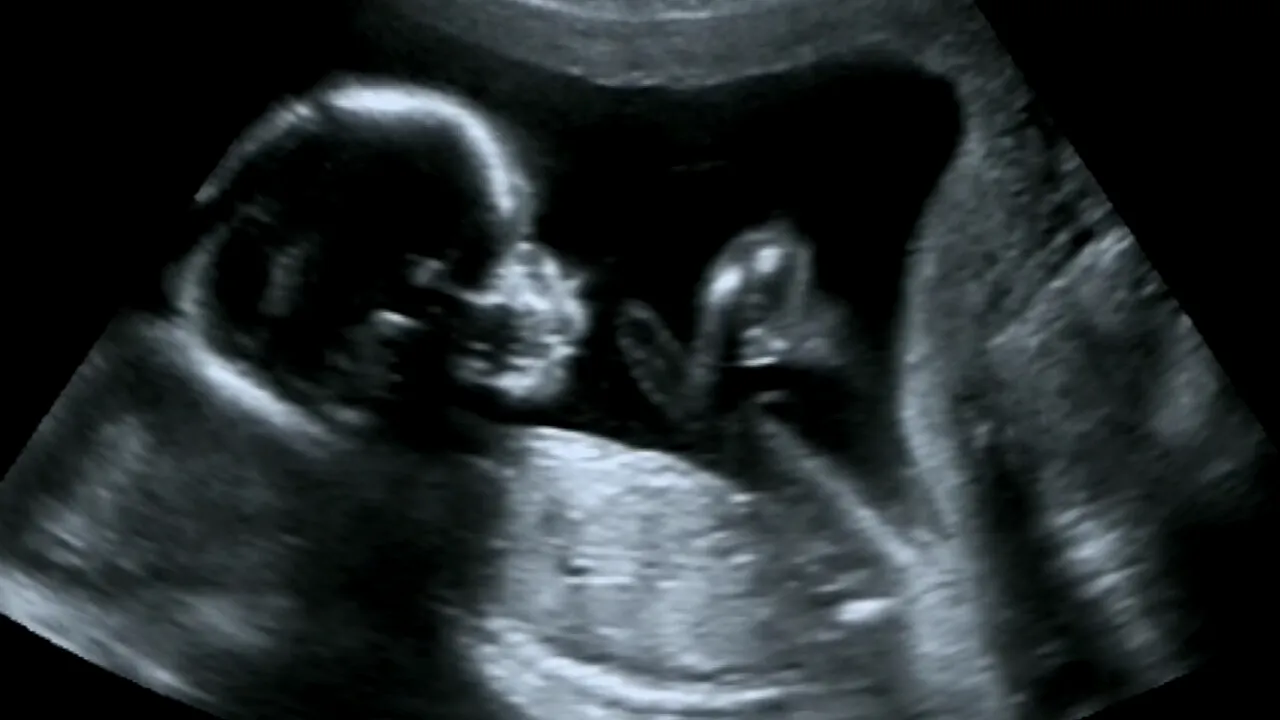

Atunci când o femeie este însărcinată, abia așteaptă următoarea ecografie pentru a-și vedea bebelușul, pentru a-i surprinde fața, mâinile, ochii. În plus, ecografia în timpul unei sarcini este esențială pentru a observa dezvoltarea copilului.

Însă, atunci când faci un o scanare RMN a bebelușului, lucrurile stau complet diferit. RMN-ul pentru făt este recomandat pentru a ”evalua anomaliile din creierul, coloana vertebrală și corpul copilului”, potrivit Spitalului de Copii din Philadelphia.

Însă… imaginile unui RMN sunt de-a dreptul terifiante! Un aparat RMN folosește câmpuri magnetice și unde radio pentru a crea imagini în secțiune transversală ale corpului. Procedura emană o vibrație foarte diferită față de ultrasunete și  arată complet diferit pentru cei care își imaginează că acestea sunt similare cu cele ce pot fi observate prin ultrasunete.

Mai exact, imaginile te pot speria serios, mai ales că bebelușul arată ca un mic demon din altă dimensiune.

Nu de puține ori, acest tip imagini se postează pe rețelele de socializare și devin imediat virale, oamenii fiind îngroziți că un bebeluș ar putea arăta așa.